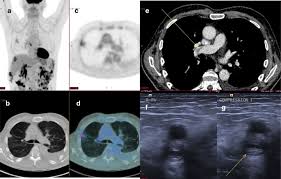

P3 03 025 Investigating Phenotypic And Genomic Heterogeneity In Malignant Pleural Mesothelioma Journal Of Thoracic Oncology

P3 03 025 Investigating Phenotypic And Genomic Heterogeneity In Malignant Pleural Mesothelioma Journal Of Thoracic Oncology from els-jbs-prod-cdn.jbs.elsevierhealth.com

Since pet scans only show the where the most tracer fluid was collected, they are an excellent tool for determining how far mesothelioma has spread. These tests are critical in diagnosing mesothelioma cancer. Imaging is important in diagnosing mesothelioma.it will provide information such as the extent of disease in the original organ and also show if the cancer has spread to. Early detection of the fatal and incurable mesothelioma and the subsequent provision of radiation, surgical and palliative asbestosis treatments are known to help a patient to have the best possible chance to extend and improve the quality of life remaining. mesothelioma, also known as malignant mesothelioma, is an aggressive malignant tumour of the mesothelium. Tongue metastasis was the first sign of malignant pleural mesothelioma detected by pet/ct. The tumor originates from cells of the visceral or parietal pleural and is linked to asbestos exposure with a median latency of 44.6 years .due to the latency between exposure and onset of mesothelioma and the ongoing use of asbestos in parts of the world, the incidence is expected to rise. ct scans and mris for mesothelioma diagnosis.

Everything you need know mesothelioma life! Some machines can do both a pet and ct scan at the same time. The qualitative assessment was statistically different (p=0.0020, χ). Malignant pleural mesothelioma (mpm) is the most common, whereas malignant peritoneal mesothelioma accounts only for. A short summary of this paper. Doctors can make a metastatic mesothelioma diagnosis through radiology imaging scans such as mri, ct or pet. Kazuhiro kitajima, hidetoshi matsuo, atsushi kono, kozo kuribayashi, takashi kijima, masaki hashimoto, seiki hasegawa, takamichi murakami, koichiro yamakado. Since pet scans only show the where the most tracer fluid was collected, they are an excellent tool for determining how far mesothelioma has spread. European journal of nuclear medicine and molecular imaging, 2014. 191 all treatments were planned based on ct and pet/ct imaging. Doctors analyze imaging scans and tissue or fluid samples to diagnose mesothelioma. Malignant pleural mesothelioma (mpm) is an aggressive thoracic malignancy with a dismal prognosis. ct scans and mris for mesothelioma diagnosis.